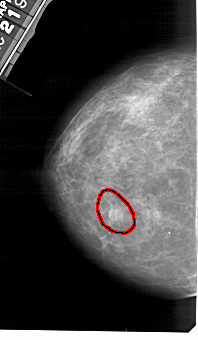

A_1362_1.RIGHT_MLO

RIGHT_CC LINES 4876 PIXELS_PER_LINE 2941 BITS_PER_PIXEL 12 RESOLUTION 43.5 NON_OVERLAY

FILE: A_1362_1.LEFT_MLO.OVERLAY

TOTAL_ABNORMALITIES 1

ABNORMALITY 1

LESION_TYPE MASS SHAPE IRREGULAR MARGINS ILL_DEFINED

ASSESSMENT 4

SUBTLETY 5

PATHOLOGY BENIGN

TOTAL_OUTLINES 1

BOUNDARY